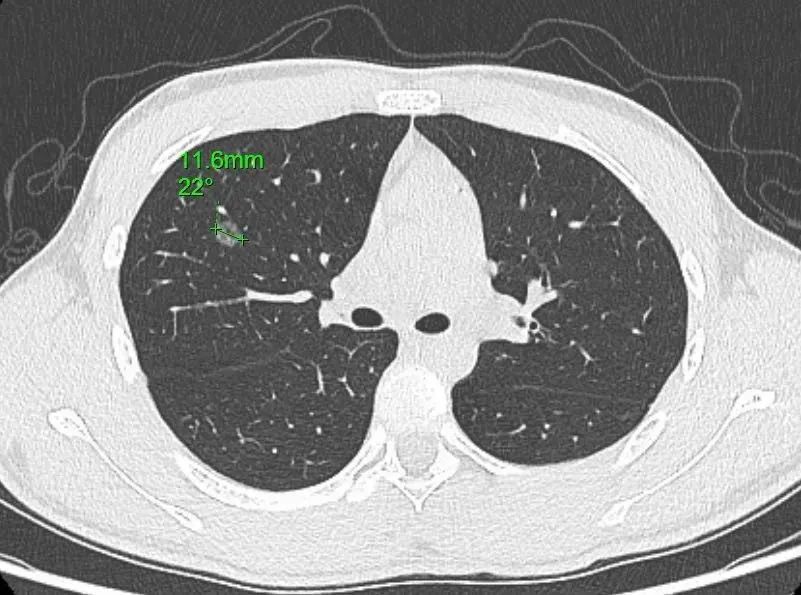

小亮的肺结节位于右上肺前段(1.16cm)。今年1月,父亲带着小亮和小亮外婆前往医院进一步就诊。通过复查胸部CT,胸心外科张晓明主任发现两人的肺结节都有不同程度增大,需尽早手术。小亮和外婆当天就办了入院,并安排在同一天手术,好在两人手术都很成功。